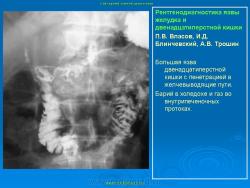

Пищеварительная система. Рентгенодиагностика язвы желудка и 12-ти перстной кишки. +

Рентгенодиагностика язвы желудка и 12-ти перстной кишки.